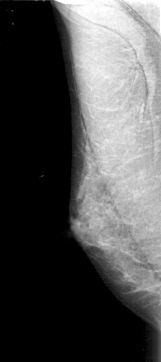

D_4165_1.RIGHT_MLO

RIGHT_MLO LINES 5056 PIXELS_PER_LINE 2251 BITS_PER_PIXEL 12 RESOLUTION 43.5 NON_OVERLAY